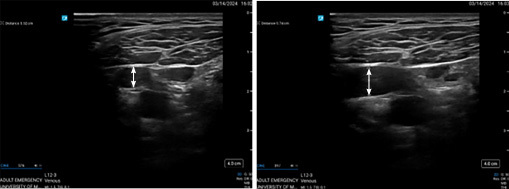

An elevated jugular venous pressure (JVP) is another marker for volume overload and increased right heart pressures. The clinical assessment of JVP can be difficult, especially in obese patients. Ultrasound measurement of JVD is performed using the linear probe with the patient in a semi-recumbent position (head and neck elevated to 45 degrees). The IJV diameter (JVD) is assessed within 5 cm of the jaw angle. The JVD is measured at rest and while performing a Valsalva maneuver.54

In patients without acute heart failure the JVD typically is only 0.1 cm to 0.15 cm at rest, but it can increase to approximately 1 cm during Valsalva. The JVD ratio then is calculated based on measurements at rest and during Valsalva. When intravascular congestion is present, the JVD increases at rest and the JVD ratio decreases. A JVD ratio of less than 4 is suggestive of intravascular congestion.59 (See Figure 3.)

Figure 3. Measurement of Internal Jugular Vein Diameter (JVD) in Patient with Acute Decompensated Heart Failure |

Patient at rest (left, JVD = 0.52 cm) and performing Valsalva (right, JVD = 0.74 cm) shows a JVD ratio of 1.42, which is less than 4, suggestive of intravascular congestion. Source: Jonathan Hurst, MD. |

Pellicori et al evaluated the JVD ratio in patients with HF in an outpatient setting. The patients with a JVD ratio in the lower tertile had a 10-fold increased risk of death or admission for HF as compared to the patients in the upper tertile.60